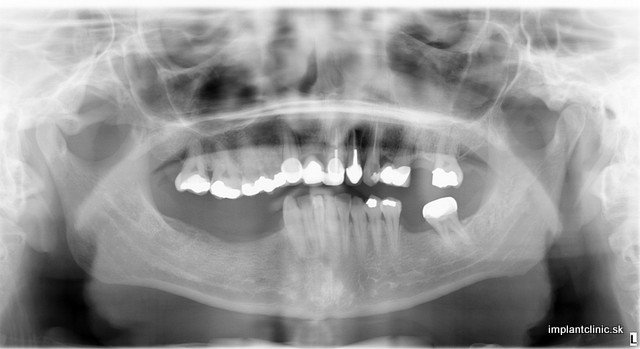

Snímok pred ošetrením

Natália túžila mať dokonalé zuby a dokonalý úsmev. Rozhodla sa podstúpiť radikálnu zmenu. Jej ošetrenie zahŕňalo dve extrakcie, päť zubných implantátov, sedem implantových koruniek, pätnásť celokeramických koruniek, päť kovokeramických koruniek.